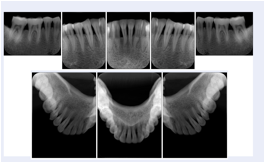

In most standard cases, images are oriented in structured layouts. These structured displays are useful to be shared between providers for reference purposes.

Table OO.1.1-1 shows structured display standard templates, where Viewset ID is based on the Japanese Society for Oral and Maxillofacial Radiology (JSOMR) classification provided by JIRA (Japan Medical Imaging and Radiological Systems Industries Association, www.jira-net.or.jp). Expected or typical teeth to be imaged location, region and designation codes are based on ISO 3950-2010, Dentistry - Designation system for teeth and areas of the oral cavity. For all the hanging protocols listed in OO.1.1-1, the value to use for Hanging Protocol Creator (0072,0008) is "JSOMR" and the value to use for Hanging Protocol Name (0072,0002) does not include "JSOMR" (e.g., "DL-S001A", not "JSOMR DL-S001A").

Table OO.1.1-1. Hanging Protocol Names for Dental Image Layout based on JSOMR classification